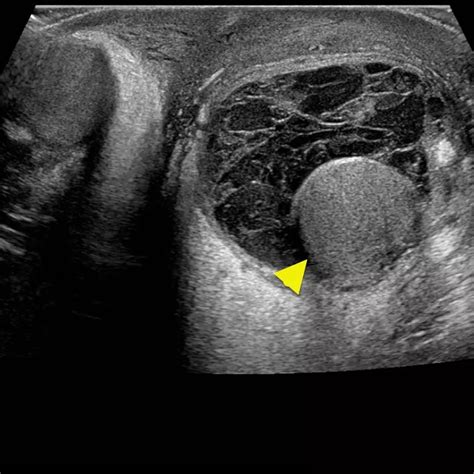

An ultrasound allows the physician to clearly distinguish between a solid mass—which requires further investigation—and a fluid-filled cyst, which is typically benign. If you have been looking for Testicular Cyst Images, you have likely seen ultrasound depictions showing dark, well-defined areas; these represent the fluid within the cyst, contrasting with the more textured appearance of the testicle itself.

Scrotal Ultrasound Imaging using sound waves Differentiates between solid masses and fluid-filled cysts.